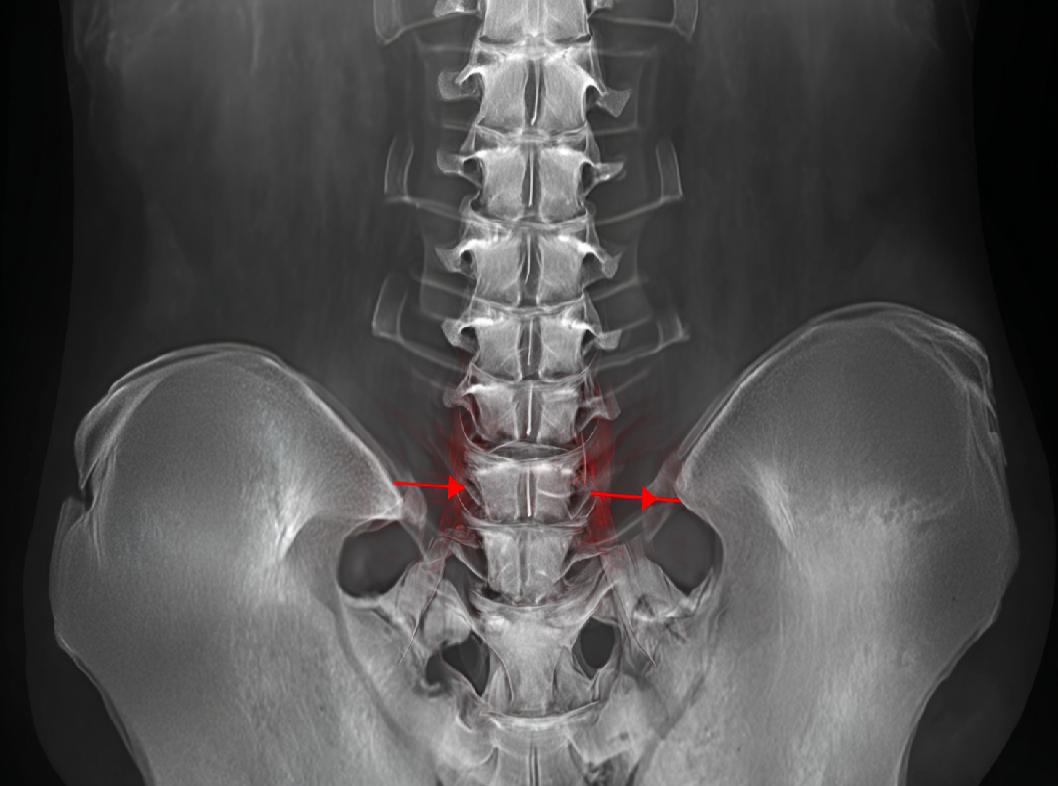

Диагноз ПК обычно ставится на основе клинического осмотра, рентгенологических исследований и, при необходимости, дополнительных методов, таких как компьютерная томография (КТ) или магнитно-резонансная томография (МРТ). Лечение может варьироваться от консервативных методов, таких как носка корсета и реабилитационных упражнений, до хирургического вмешательства в случаях смещенных или нестабильных переломов. Общий подход к лечению определяется индивидуальными характеристиками пациента и характером травмы.

Важно подчеркнуть, что при наличии подобных симптомов необходимо обратиться к врачу для проведения тщательного обследования и диагностики, включая рентгенографию или другие методы изображения, чтобы точно установить наличие и характер перелома крестца.